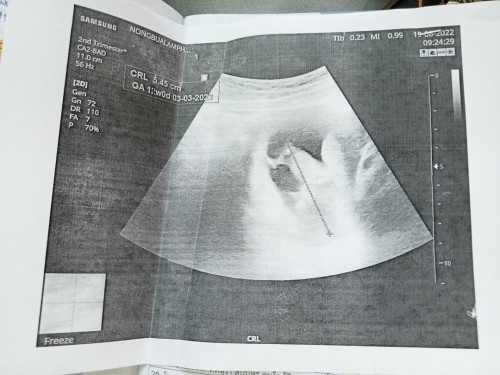

เเม่ๆช่วยดูทีค้าอันไหนคือตัวน้องดูไม่เปนเยยท้องเเรก 12สัปดา5วัน